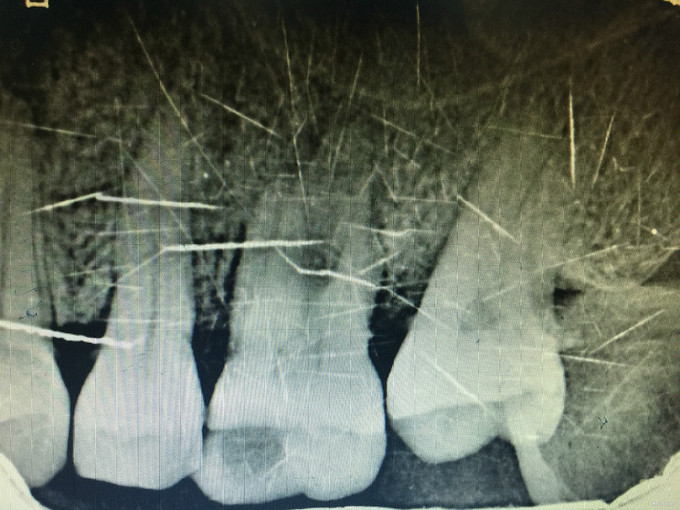

临床检查:26近中龋坏可探及穿髓点,无窦道,探疼(+),冷(++),叩(-),松动度(-),牙周红肿,牙石1度 辅助检查:X线示26龋坏累积髓腔。

诊断:26牙髓炎 治疗:经患者知情同意后,26局麻去腐降牙合,开髓拔髓寻找根管口,建立直线通路,扩通根管,确定工作长度。S3/EDTA凝胶镍钛器械,次氯酸钠冲洗根管,预备至35/04,氢氧化钙诊间封药,一周后复诊,试主尖X线示恰充,试干根管,导AH-PLUS糊剂,VDW热压胶垂直加压根充,术后见根管恰充,暂封调合抛光。树脂充填。